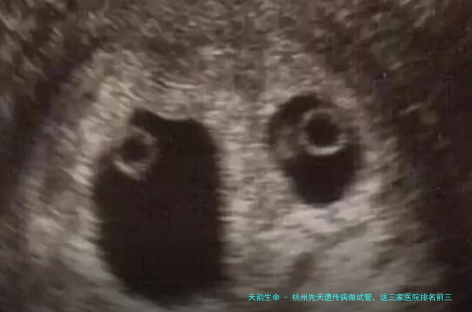

术语解释: - 试管婴儿技术:是一种辅助生育技术,包括体外受精 - 胚胎移植(IVF - ET)及其衍生技术,如一代试管婴儿主要适用于女性一方要素导致的不孕;二代试管婴儿主要适用于男方要点导致的不育;三代试管婴儿主要适用于有遗传疾病风险的夫妇,可在胚胎移植前进行遗传学诊断和筛查。 - 夫精人工授精:是将丈夫的精液经过处理后,在女方排卵期间注入女方生殖道内,以替代使女性一方受孕的一种助孕技术。 - 供精人工授精:是指使用供精者的精液进行的人工授精,适合于丈夫无精子症等情况。 - 临床妊娠率:是指胚胎移植后,通过超声检查观察到宫内妊娠囊的妊娠比例,是衡量试管婴儿技术的一个重要标准。 - 冻融胚胎移植周期:是将冷冻保存的胚胎解冻后进行移植的过程。